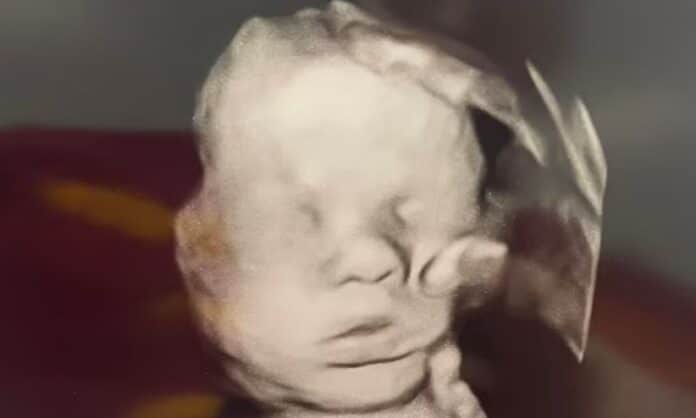

Μια γυναίκα από το Κεντάκι πιστεύει ότι το μωρό της έχει ευλογηθεί από «το χέρι του Θεού» μετά την εμφάνιση μιας παράξενης σκιάς στον υπέρηχο της.

Η σάρωση των 32 εβδομάδων φαίνεται να δείχνει ένα μεγάλο χέρι να χαϊδεύει το κεφάλι του αναπτυσσόμενου εμβρύου στη μήτρα.

διαγνώστηκε με καρδιακή πάθηση νωρίς στην εγκυμοσύνη.Ο υπέρηχος έχει γίνει viral στο διαδίκτυο, με τους ανθρώπους να αποκαλούν την εικόνα «καταπληκτική» και «θαύμα».

Άλλοι έχουν προτείνει ότι είναι στην πραγματικότητα το χέρι του μωρού, διευρυμένο και παραμορφωμένο κατά τη διάρκεια του υπερηχογραφήματος.

Πήρε μαζί της τη μικρότερη κόρη της, Μπέιλι, στο ραντεβού για υπερηχογράφημα, όπου η Μπέιλι ήταν η πρώτη που εντόπισε το γιγάντιο χέρι πάνω από το πρόσωπο του μικρού αδελφού της.